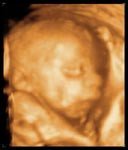

Gracias a la ciencia, los métodos de diagnóstico prenatal son cada vez más complejos. La ecografía tridimensional en tiempo real en movimiento o 4D es una nueva tecnología al servicio del seguimiento clínico del embarazo que aporta más...